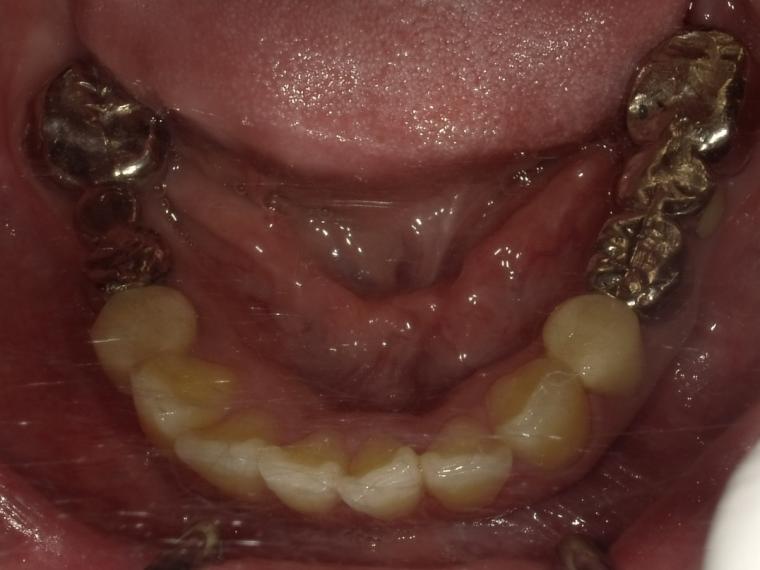

BEFORE

36歳女性/下2本欠損/インプラント埋込手術

左下のブリッジが割れそうでご来院の患者さんです。

保存状態が厳しかった為、第一大臼歯と第二大臼歯が抜歯となりました。

第一大臼歯と第二大臼歯をインプラント、第二小臼歯をクラウンでの治療を希望されました。